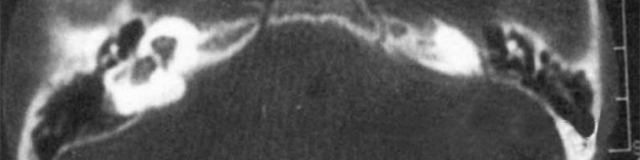

主要依靠颞骨高分辨CT和内耳MRI。

双侧内耳畸形:左侧无内耳迷路及内耳道机构,为米歇尔畸形;右侧空耳蜗及前庭扩大,为先天性耳蜗畸形